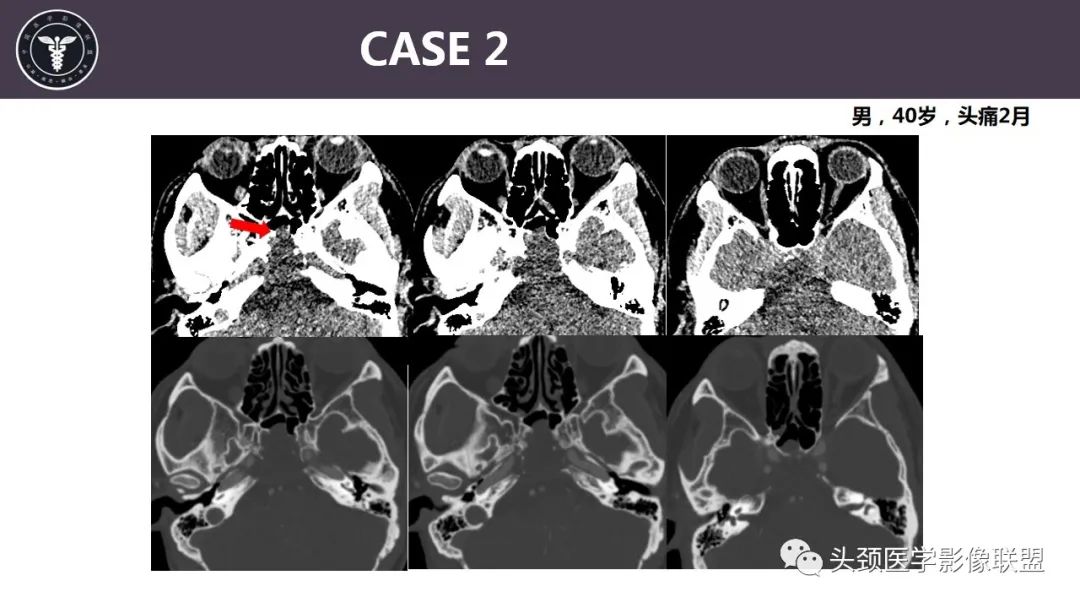

病例2